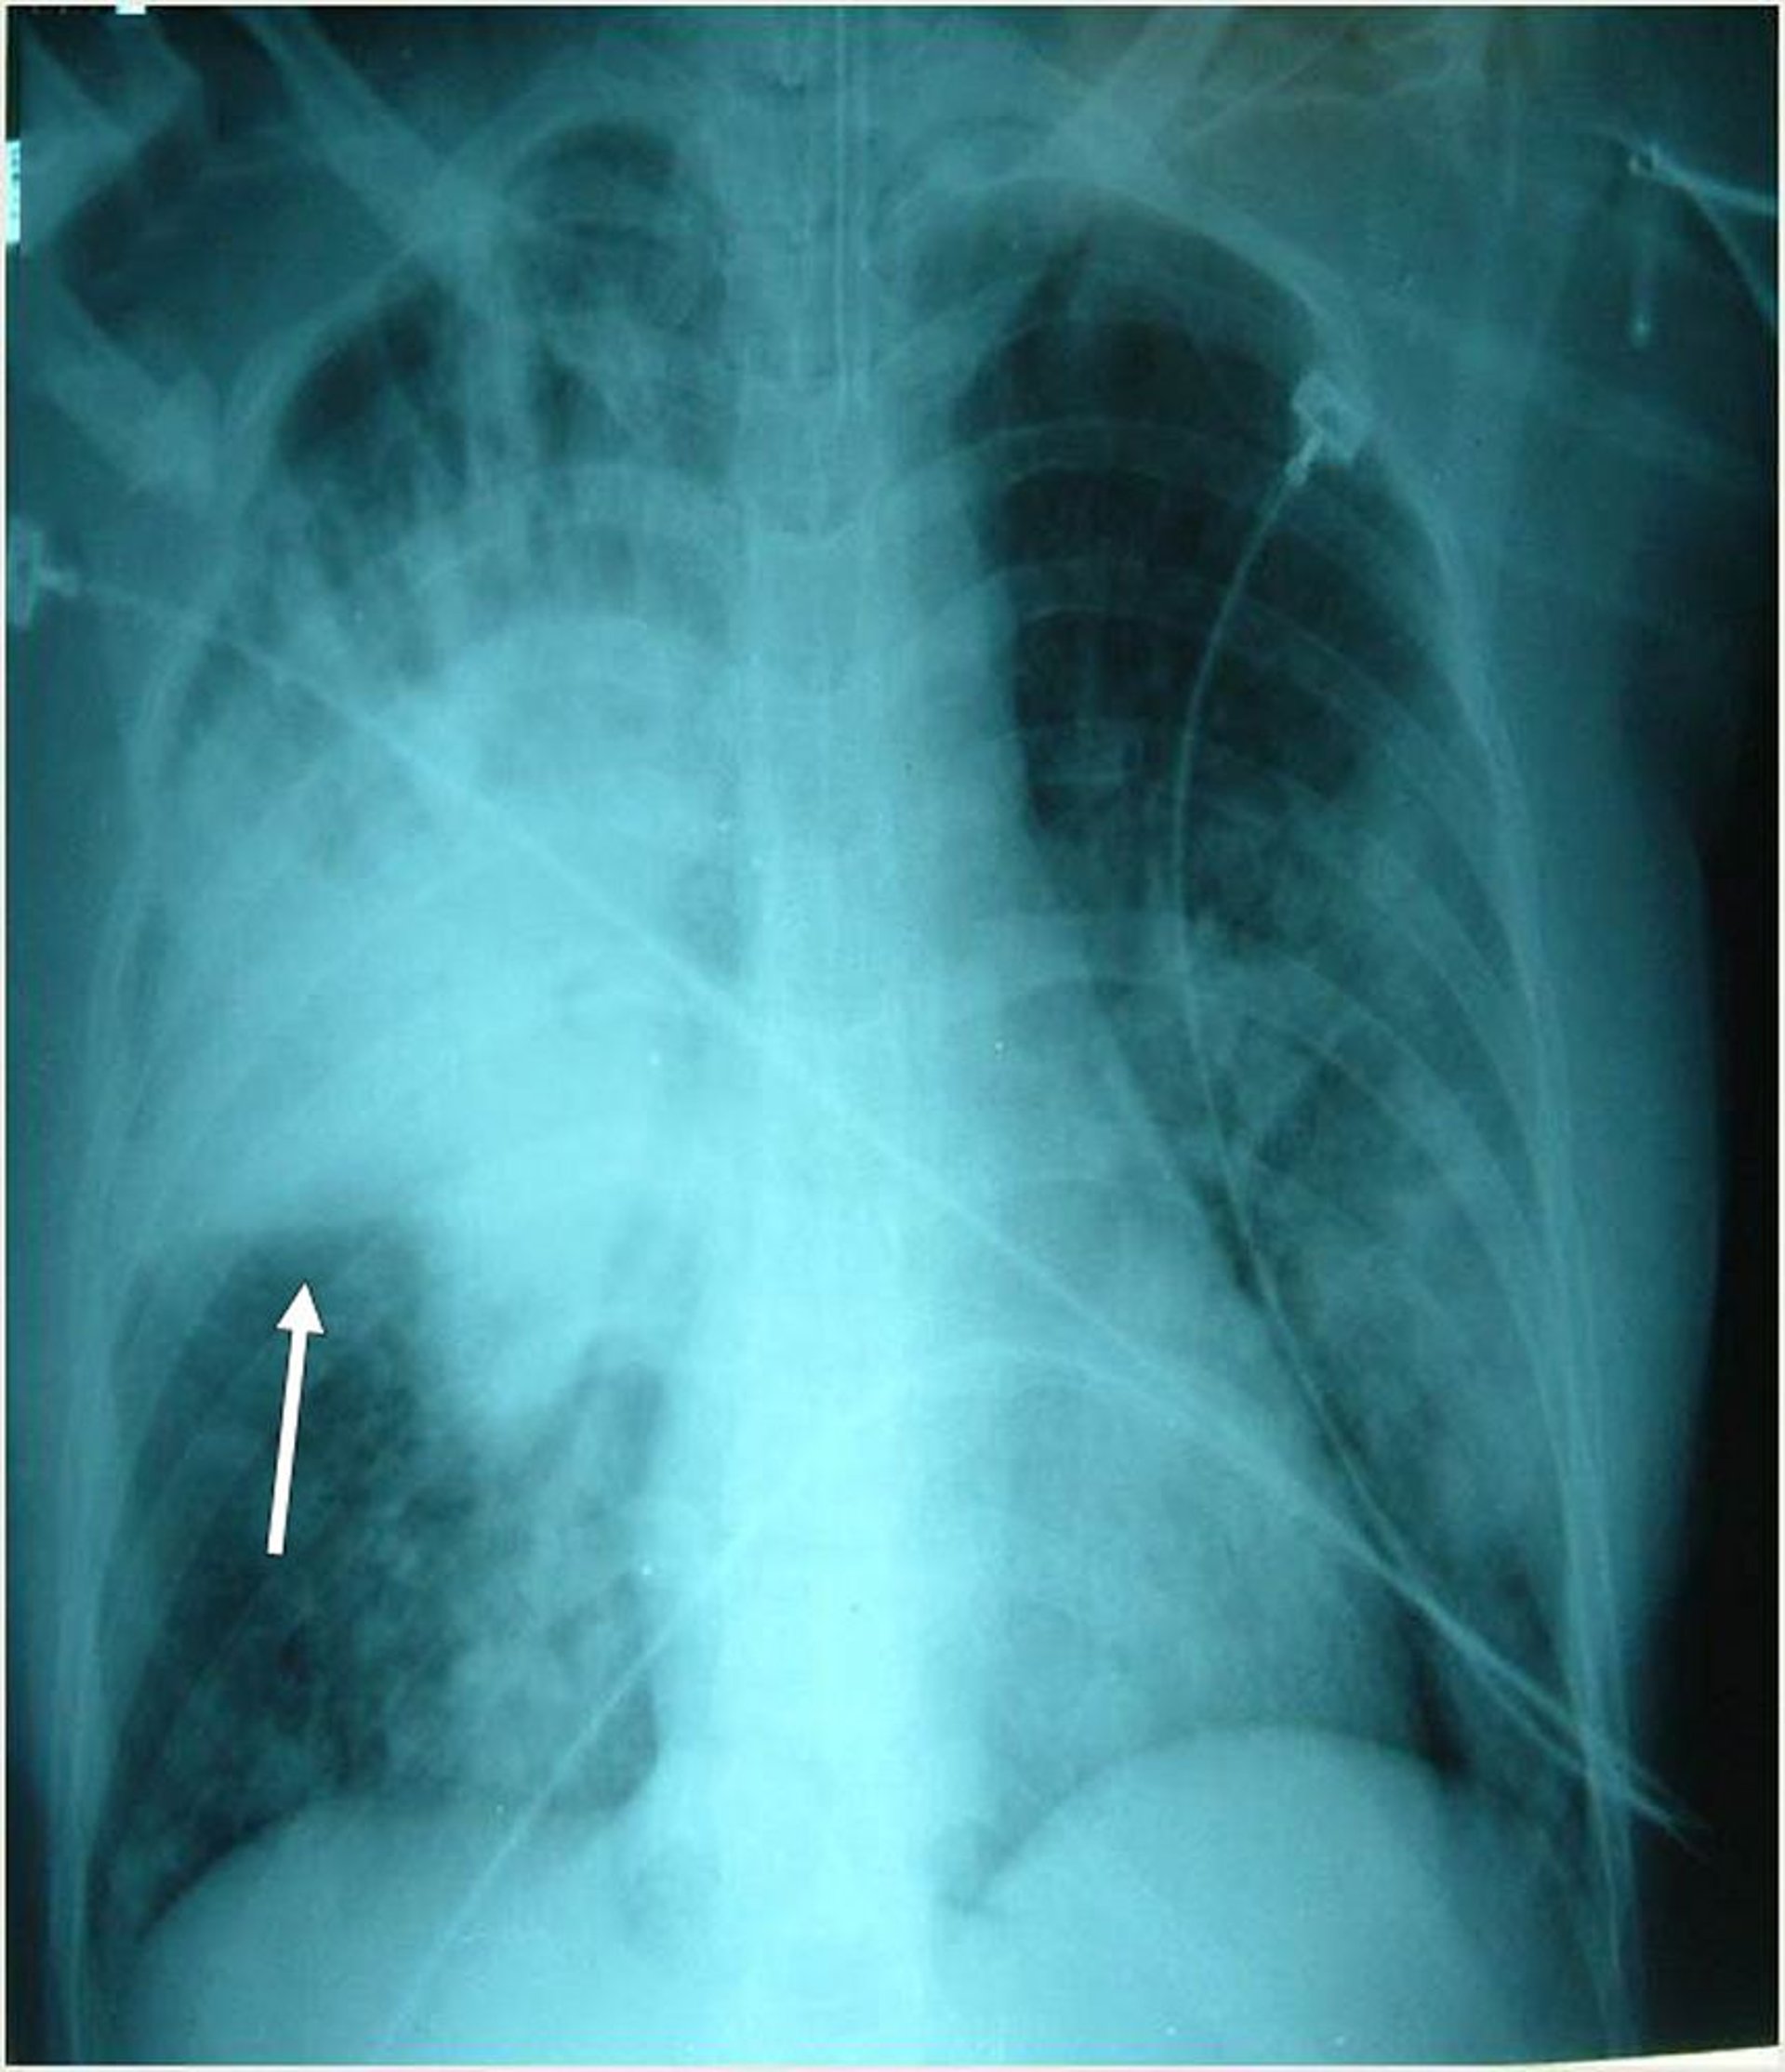

Esse paciente intubado tem múltiplos infiltrados bilaterais, mais proeminentemente no lobo superior direito. A seta indica a fissura horizontal direita.

Photo courtesy of Thomas M. File, Jr., MD MSc MACP FIDSA FCCP.